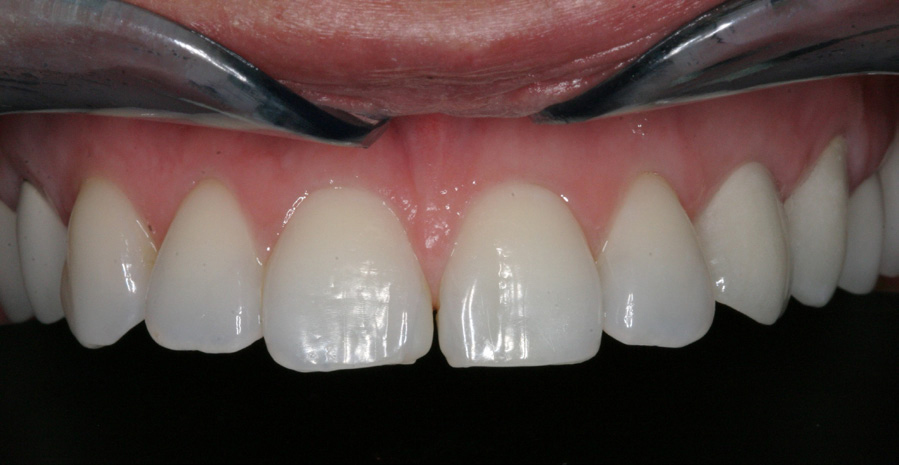

A dental implant most closely replicates natural tooth structure. Once it is osseointegrated, many patients cannot differentiate an implant from a natural tooth. Furthermore, dental implants do not decay or need root canal therapy. Even though the cost is slightly more than a bridge, it is an investment for the future, as implants usually last longer than a bridge. A 10-year report on posterior single implants shows a success rate of 97%.33 Once an implant is placed, the osseointegration and tissue healing time of approximately 4 months is necessary before a final crown is placed. A temporary crown can be placed the same day the implant is placed, but this is only for esthetics, not for function (Figure 15 through Figure 19).

Figure 15 – Extraction of anterior tooth No. 8 without detaching the gingiva.

Figure 15

Figure 16 – Extracted tooth with the root canal material (gutta percha) extending from the apex

Figure 16

Figure 17– A zircon (white) abutment was attached immediately after extraction and implant placement.

Figure 17

Figure 18 – Immediate placement of temporary crown over the abutment; laser crown lengthening was performed on the adjacent teeth to improve gingival symmetry

Figure 18

Figure 19 – Four months after surgery with temporary crown over the implant at No. 8.

Figure 19